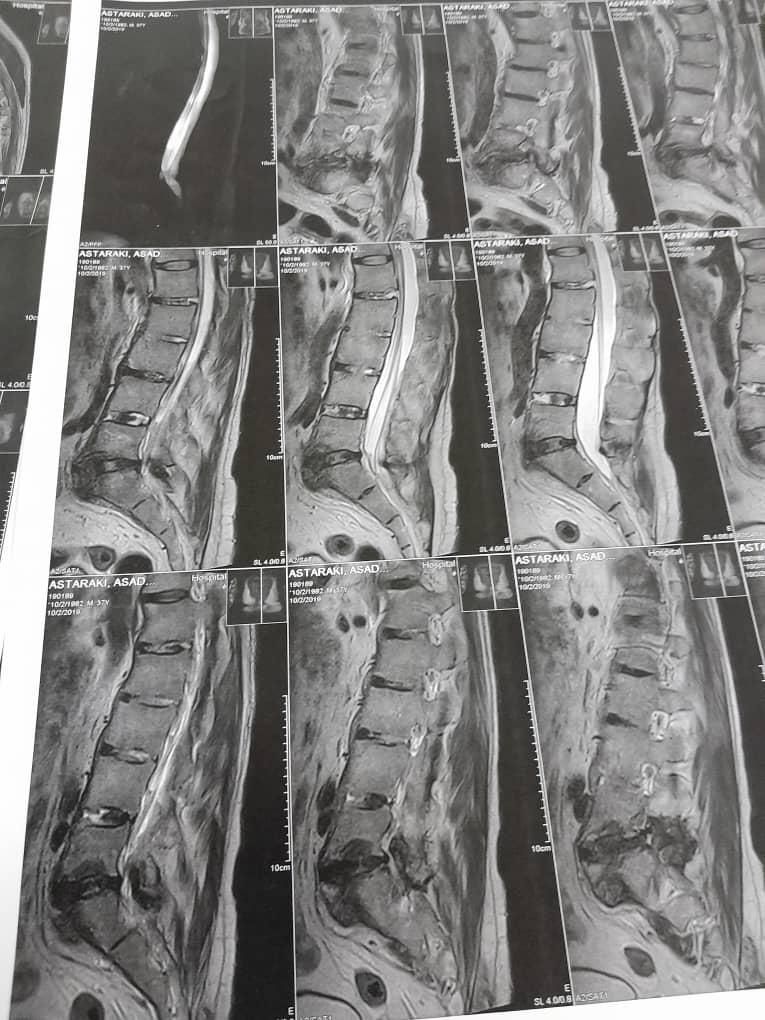

طب فیزیکی سنتی دررفتگی مفاصل دیسک کمر گردن سیاتیک

☆درمان بدون دارو●بدون عمل●بدون دستگاه و ابزار خاص☆ درمان به شیوه طب فیزیکی سنتی و چینی و هندی فقط با دست ☆برای شرح حال و نوبت ساعت ۱ ظهر به بعد تماس بگیرید☆ ☆جلسات درمانی درحال حاضر منزل بیمار انجام می شود☆ برای اقایان و ... ✅ اصلاح و درمان دیسک کمر ✅ اصلاح و درمان دیسک گردن ✅ اصلاح و درمان عصب سیاتیک ✅ اصلاح و درمان چرخش ،بیرون زدگی ، فرو رفتگی مهره کمر. ✅ اصلاح و درمان شانه یخ زده (دردکتف ویا کشیدگی تاندون ها) ✅ اصلاح و درمان تنیس البو (درد آرنج و یا کشیدگی تاندون ها) ✅ اصلاح و درمان سندرم تونل کارپال(گیر افتادن عصب دست) ✅ اصلاح و درمان(JMT) مفصل فکی:باز نشدن کامل دهان ✅ اصلاح و درمان میگرن و سر دردهای قدیمی ✅ اصلاح انگشتان ماشه ای ✅ اصلاح جابجایی لگن(کوتاهی پا) ✅ اصلاح زانو درد ✅ اصلاح خارپاشنه ✅ اصلاح دنبالچه ✅ اصلاح فلج بلز صورت ✅ اصلاح وزوز و صدای گوش ✅ کیست های چربی روی دست ✅ رگ گیری ✅ قولنج گیری ✅ هول گیری ✅ تول گیری ✅ ناف گیری 《《 جا اندازی دررفتگی های مفاصل 》》 ✅ شانه ✅ آرنج ✅ مچ دست ✅ لگن ✅ زانو ✅ مچ پا ✅ انگشتان

تصویر 1 از 2